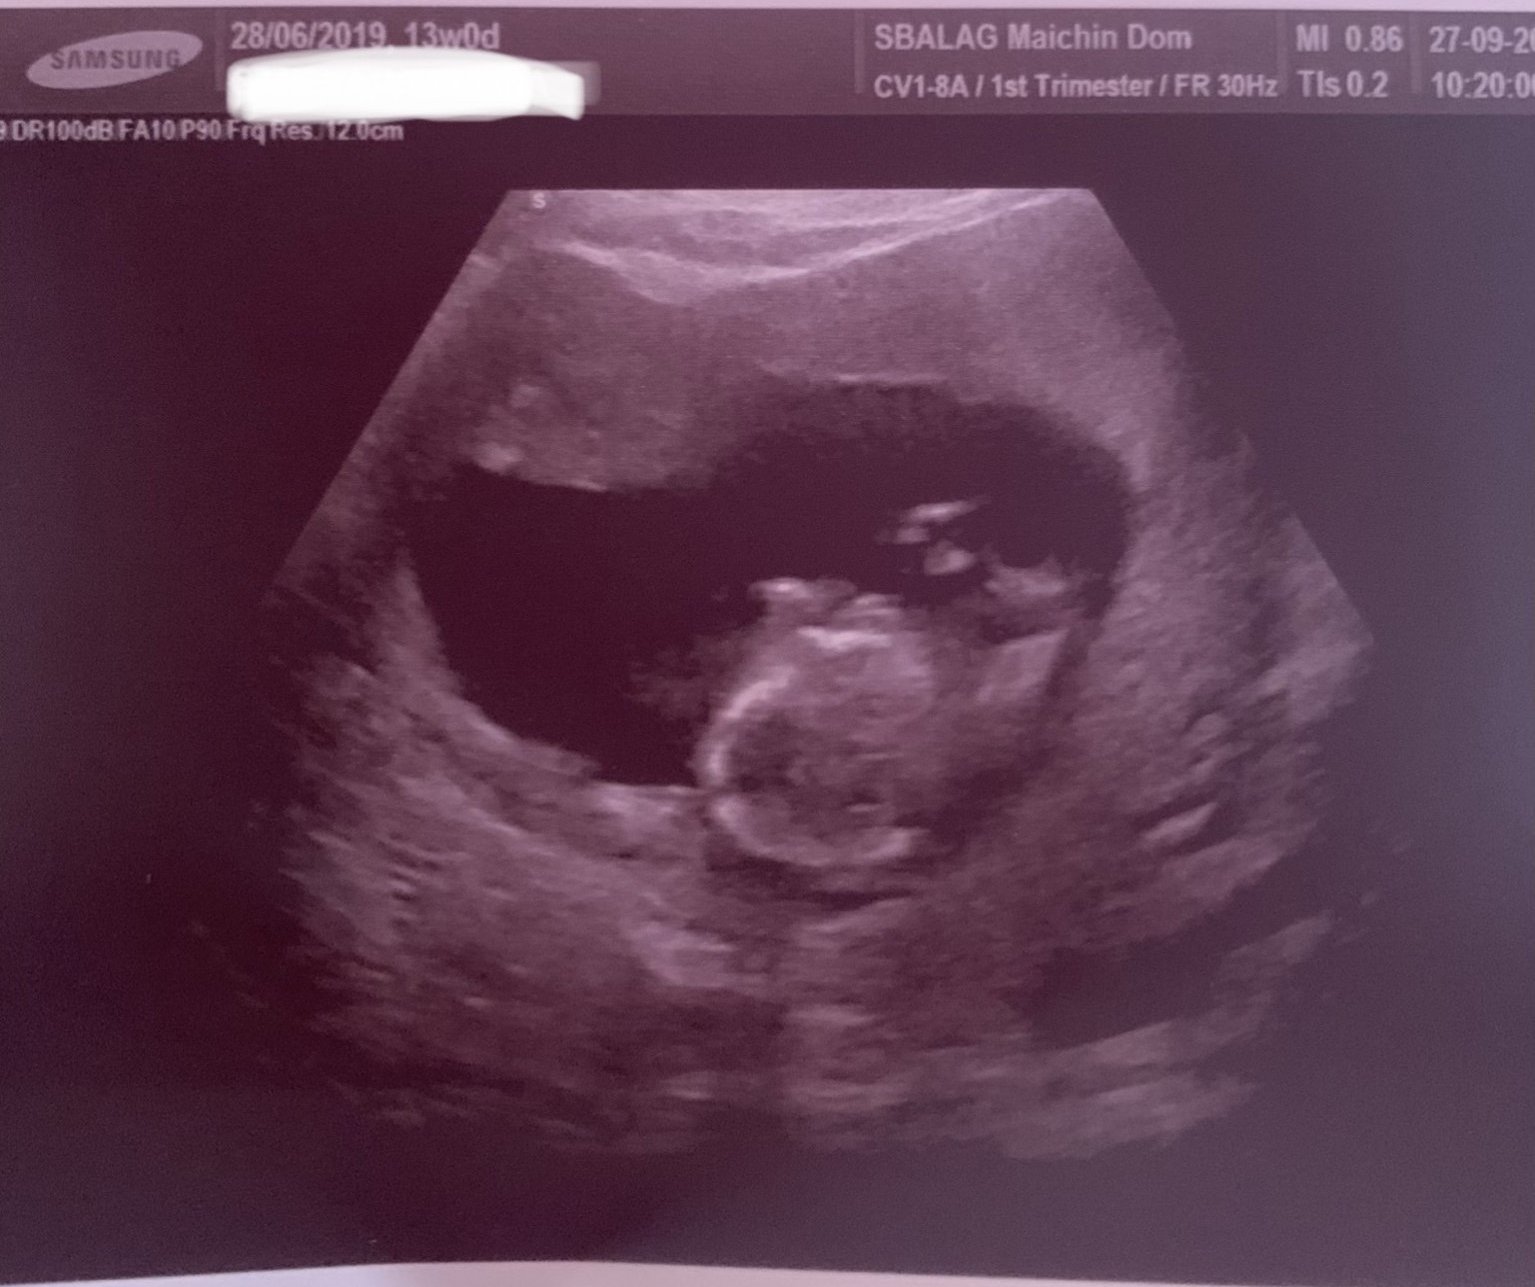

Не се връщам с добри новини.Димитрова потвърди мнението на Чачева и след като ме разпита какво тя е открила,и тя каза,че дясната ръчичка я държи беба малко по-разперено и не я мърда,което говорело за съмнение за по-къс радиус на ръката. След като видя и резултатите от бхс се развика да ходя на хорионбиопсия и да се моля бебето да е здраво😭